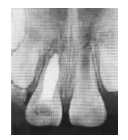

治療:11開髓,牙髓壞死,去髓。因根尖孔較大,根管長度測量不穩(wěn)定,去凈根管壁感染牙本質,生理鹽水反復沖洗并吸干,封氫氧化鈣糊劑。1周復診,檢查:11探(-),叩(-),牙齦紅腫明顯消褪;去除原充物,由于牙根未發(fā)育完全,擬行根尖誘導成形術。用Vitapex糊劑充填根管,水門汀墊底,3M樹脂充填(圖1b)。

圖1b 術后1周X線片

1個半月后復診,X線片示:11、21根尖孔未閉合,11根尖部Vitapex糊劑部分吸收,根中1/3內吸收暫停,根尖周稀疏區(qū)消失,但根尖孔無閉合傾向,牙根長度無明顯變化,且略短于21的牙根長度。更換11根管內Vitapex糊劑(圖1c)。

圖1c 術后1個半月X線片